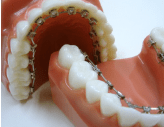

写真②:使用する装置例

写真③:使用する装置例